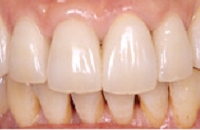

セラミックに換えた状態

セラミックの歯に換えました。

金属の黒ずみが消えました。